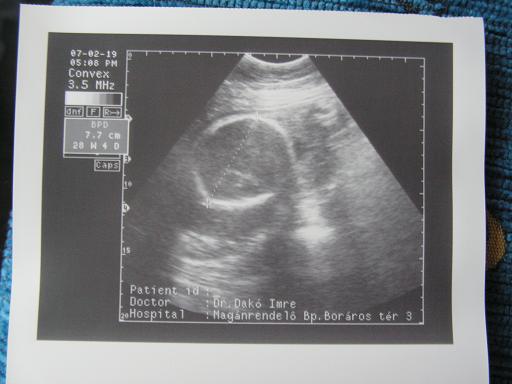

Ja, nekem is van uh-hírem. (Képem nincs, még a nemét sem nézték.

) Egy jó és egy rossz hír (megint). A jó: felszívódtak a ciszták a baba fejében. (Egy hét alatt!) A rossz: meszes a lepény. Utánanézek majd, mi mindent jelent ez. Az u-os nagyon csóválta a fejét, de a genetikus orvos, akivel utána beszéltünk az eredményekről, nem tulajdonított nagy jelentőséget ennek. Azt mondta, akkor lenne baj, ha a baba nem fejlődne jól. Ehhez képest 2 héttel nagyobbnak tűnt a koránál.

És meghaladta az 1 kilót! MAjd elmondom azt is, mit mondott a dokim (délelőtt hívom).